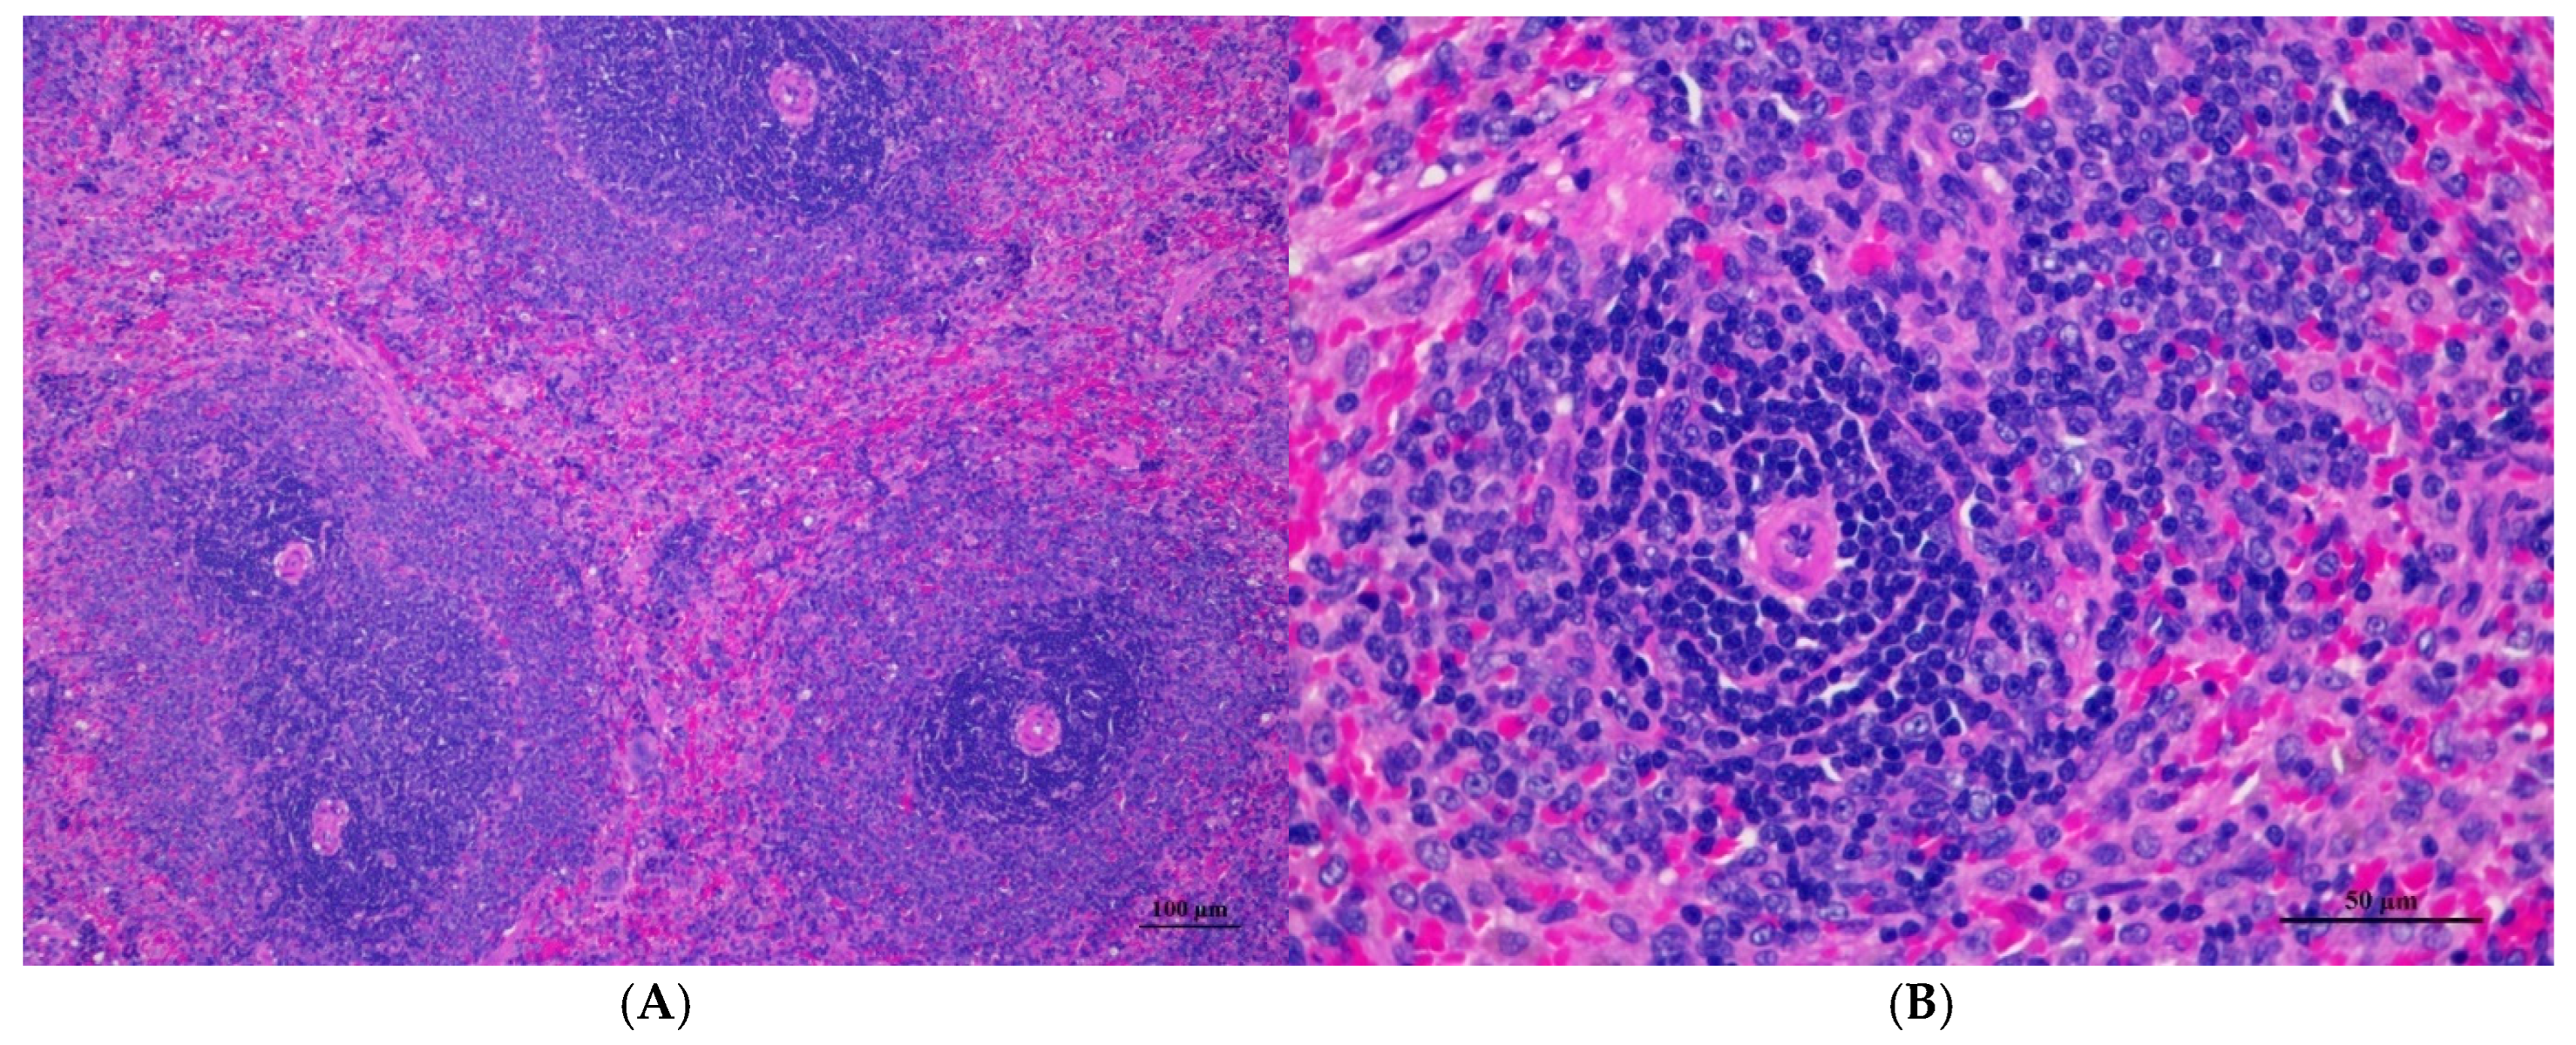

Figure 4.

Histopathological examination of rat splenic tissue in acute toxicity from single oral dose of CDF displayed normal microscopic structure. (A) Splenic tissue showed intact structure with distinct white pulp and red pulp regions (100×, H&E). (B) High magnification reveals normal lymphoid follicles with intact germinal centers. No histopathological abnormalities were observed (400×, H&E).

Figure 9.

Histopathological examination of rat splenic tissue in sub-acute toxicity from daily (28 days) fed oral dose of CDF showed normal microscopic appearances. (A) Splenic tissue exhibited well-organized white pulp, marginal zone, and red pulp (100×, H&E). (B) High magnification showed an unremarkable lesion of red pulp. The lymphoid follicle displayed an intact germinal center with densely packed lymphocytes (400×, H&E).

3.1.7. Histopathological of Male and Female Rats

Histopathological findings for male and female rats administered CDF at 175, 550, and 2000 mg/10 mL/kg are summarized in Table 12 and Table 13, respectively. In male rats (Table 12), the 2000 mg/kg group exhibited interstitial pneumonitis (IP) in the lungs of four out of five animals. The 550 mg/kg group showed mild hepatic vacuolation (HV) and hepatic degeneration (HD) in two out of five animals as well as IP in the lungs (four out of five). The 175 mg/kg group presented with mild HV and HD in the liver (one of five) and IP or normal alveolar septal thickness (N AVT) in the lungs (two of five each). The propylene glycol control group displayed mild HV and HD in the liver (two of five) and IP or N AVT in the lungs (three of five and one of five, respectively). In female rats (Table 13), all doses, including the control, resulted in IP in the lungs of the majority or all animals. The 550 mg/kg group also showed mild HV and HD in the liver (one of five). No histopathological alterations were observed in the kidneys, hearts, or spleens of either sex across all treatment groups.

Histopathological analysis revealed generally unremarkable findings in the liver, kidney, heart, and spleen, with only minor, scattered hepatocellular swelling and vacuolation in the liver, mild renal tubular degeneration in limited kidney areas, and focal myocardial vacuolation and lymphoid aggregation in the heart. Conversely, the lung exhibited significant pathological changes, characterized by alveolar septal thickening due to severe interstitial infiltration of lymphocytes and other mononuclear cells, nodular lymphoid aggregations, alveolar septal engorgement and hyperemia, alveolar edema, and multifocal mild alveolar hemorrhage, suggesting a potential site of inflammatory response.

3.2.8. Histopathological of Male and Female Rats for 28 Days

For male rats (Table 28), all treated groups, including the control, exhibited mild hepatic vacuolation (HV) and hepatic degeneration (HD) in the liver. The 1000 mg/kg and 500 mg/kg groups showed HV/HD in four out of five cases, the 250 mg/kg group in five out of five cases, and the control in three out of five cases. Interstitial pneumonitis (IP) was observed in the lungs of all groups, with varying incidence. The satellite 1000 mg/kg group showed HV/HD in the liver (one of five) and IP, normal with alveolar septal thickness (N AVT), and normal with alveolar hyperemia (N AVHy) in the lungs. No histopathological changes were observed in kidneys, hearts, or spleens.